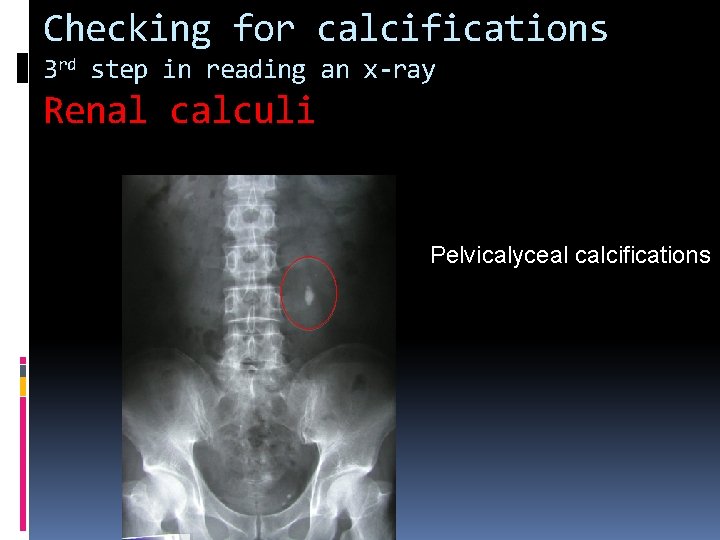

Checking for calcifications 3 rd step in reading an x-ray Renal calculi Pelvicalyceal calcifications